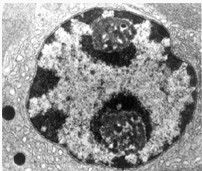

1.抗炎作用:本产品可减轻和防止组织对炎症的反应,从而减轻炎症的表现。激素抑制炎症细胞,包括巨噬细胞和白细胞在炎症部位的集聚,并抑制吞噬作用、溶酶体酶的释放以及炎症化学中介物的合成和释放。

2.免疫抑制作用:包括防止或抑制细胞介导的免疫反应,延迟性的过敏反应,减少T淋巴细胞、单核细胞、嗜酸性细胞的数目,降低免疫球蛋白与细胞表面受体的结合能力,并抑制白介素的合成与释放,从而降低T淋巴细胞向淋巴母细胞转化,并减轻原发免疫反应的扩展。可降低免疫复合物通过基底膜,并能减少补体成份及免疫球蛋白的浓度。